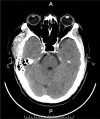

Diagnoses: Computed tomography (CT) scan showed the lesion across the zygomatic arch, with many calcified nodules differ in sizes and no erosion to the bone, magnetic resonance imaging (MRI) showed an oval lesion with hypointense and isointense on T2-weighted imaging within the temporal muscle, and preoperation diagnosis was hemangioma.